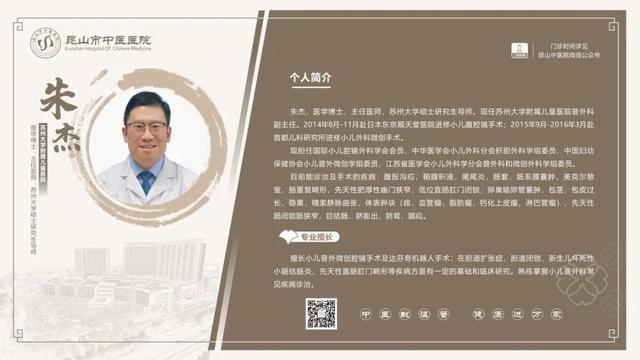

6��23��-6��29��������ר�ҳ���һ����

6��23��-6��29�������dz���ר�ҽ���